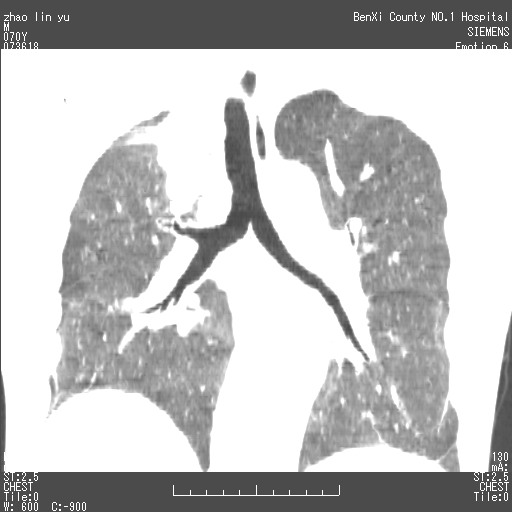

以下是引用王靖旗在2007-7-10 17:12:00的发言:[br] 男、70、咳嗽两个月,半年前换瓣手术,胸片未见异常,于昨天行x片发现右肺上野大片影,行ct扫描,这里是减薄图像,余肺正常。明天晚上会有增强扫描片,到时我会上传。[br][br] 冠状位请大家细看,应该是有意义的,[br][br] 请大家先看平扫发表意见。[br][br]

[br]冠状面[br]